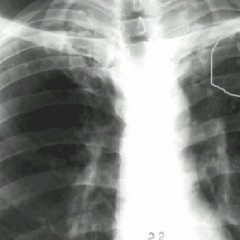

Инфильтративный туберкулез легких характеризуется очагами инфильтрации, проявляющимися на рентгенограмме в виде белесых затемнений с неровными краями. Наиболее распространенная локализация – верхние доли легких. От затемненного участка можно проследить «дорожку» к легочному корню.

На снимке участок инфильтрации (затемнение) без четких границ.